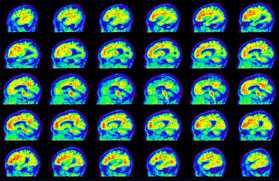

Head / Case5 : Amyloid

Sagittal

Courtesy : Kindai University Hospital

- Imaging protocol

- Injected dose: 4.27 MBq/kg, 18F-Flutemetamol

- Uptake time: 99 minutes

- Scan time: 20 minutes